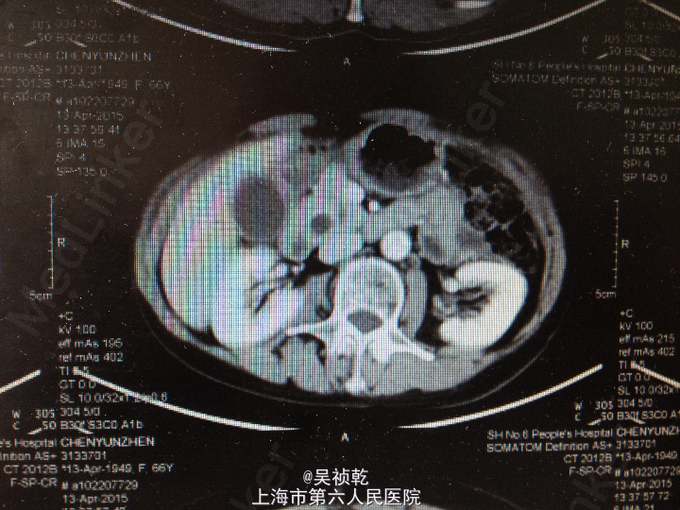

查体:皮肤巩膜无明显黄染,腹部平坦,未见明显胃肠型及异常隆起,全腹软,右上腹部压痛不明显,无反跳痛,无肌卫,无腹部反跳痛,全腹无包块,肝脏肋下未触及,脾脏肋下未触及,无肝区叩击痛,Murphy’s征阴性,肠鸣音正常,移动性浊音-。 辅查:血常规(2015-4-1):WBC:5.9×109/L,N:57.6%,RBC:4.17×1012/L,Hb:127g/L,PLT:196×109/L。肝功能:ALT:109U/L,AST:87U/L,TB:18.6umol/L。肿瘤标记物:AFP:2.7ug/L,CEA:4.71ug/L,CA19-9:37.19KU/L。 2015-4-13 上腹部MRI报告:1.胆总管下段异常信号,胆总管、胰管轻度扩张,胆总管下段结石可能大,必要时MRI增强检查,排除胆总管下段占位。2.胆囊颈结石,胆囊增大。3.附见;肝脏左叶囊性病灶。 2015-4-14上腹部增强CT报告:1.胆总管下端异常强化,结石可能,肝内外胆管及主胰管扩张,胆囊增大,必要时MRI增强进一步检查。2.肝脏小囊肿。

1. 患者入院后于4.13无明显诱因下出现右上腹疼痛,压痛明显,拒按。结合腹部CT及MRI影像学表现,胰胆管明显扩张,考虑急性胰腺炎发作。辅查:2015-4-14 生化检验报告:淀粉酶(干式) 1640 U/L ↑。生化检验报告:总蛋白 61 g/L ,白蛋白 36 g/L ,白/球比例 1.4 ,谷丙转氨酶 218 U/L ↑,谷草转氨酶 183 U/L ↑,γ-谷氨酰酶 548 U/L ↑,总胆红素 13.3 μmol/L ,直接胆红素 5.4 μmol/L ,肌酐 66 μmol/L ,血清钾 4.3 mmol/L ,血清钠 142 mmol/L ,血清氯 106 mmol/L ↑。门诊化验检验报告:白细胞 6.3 *10^9/L ,红细胞 3.84 X10^12/L ,血红蛋白 117 g/L ,细胞比积 35.9 % ,血小板 197 X10^9/L ,中性细胞百分比 58.7 % 。甲胎蛋白(AFP) 2.68 ng/mL ,癌胚抗原(CEA) 4.99 ng/mL ,糖类抗原(CA125) 6.91 U/mL ,糖类抗原(CA199) 39.45 U/mL ↑。处理:予禁食,查血、尿淀粉酶,抑酸、保肝、补液支持治疗,经治疗后症状缓解。 2. 因患者无黄疸,为进一步明确胆总管梗阻原因,4.16 行ERCP+ERBD+十二指肠乳头活检术。 检查治疗经过:十二指肠镜进入十二指肠,降部内侧见乳头,十二指肠乳头肿大,粘膜面外观正常,触之易出血。BOSTON-Jagwire导丝留置胰管,BOSTON-Jagwire导丝进入胆管引导COOK-FS-OMNI导管造影,胆管显影,胆管扩张,胰管造影胰管扩张。胆管胰管内未见充盈缺损。十二指肠乳头开口处取四块活检。放置辛菖猪胆道引流管(8.5F,6cm),辛菖胰管引流(F5,4cm),引流畅。结合MRI及CT考虑壶腹部占位可能。十二指肠乳头活检病理:绒毛状腺瘤伴部分腺体重度不典型增生,局灶癌变。 3. 患者术前诊断为十二指肠壶腹部癌,于4.23 行剖腹探查,胰十二指肠切除术。术中见:见腹腔内无腹水,腹膜、盆腔内、大网膜、肝脏、肝十二指肠韧带、胰腺周围、腹腔动脉周围、肠系膜根部、腹主动脉旁等无转移性结节和肿大淋巴结。探查见此患者左右肝胆管的汇合处接近胆胰管汇合处,右侧肝胆管壁水肿增粗,十二指肠乳头部肿块大小0.3cm,行胰十二指肠完整切除。 4. 术后病理检查报告:下半胃、胰腺、十二指肠;标本类型:切除胰腺大小 4×4×1 CM,十二指肠长 15CM,胃小弯长 8 CM,大弯长 11CM,胆囊9×3×1.5CM;肿瘤部位:肿瘤位于十二指肠乳头,大小0.5×0.3CM;组织学类型内容: 腺癌II级;血管浸润(-),淋巴管浸润(-),神经周围浸润(-);切缘: 上、下切缘及胰腺切缘均未见癌;淋巴结:以下淋巴结均未见癌转移:胰腺旁LN:0/8枚,胃大弯LN:0/6枚,胃小弯LN:0/3枚。;淋巴结免疫反应状态: SH(+), PH(+), GH(+);肿瘤旁病变: 粘膜组织慢性炎(十二指肠乳头):腺癌II级,肿瘤侵及肌层,未累及胰腺,胰腺导管扩张,小胆管增生伴中度不典型增生。(胆囊):慢性胆囊炎伴腺体增生。肿瘤组织免疫酶标记结果:CA199(-)、CEA(+)、S-100(-)、CK19(+)、CK7(+)、CDX2(-)、CK(-)、Ki67(80%+)。